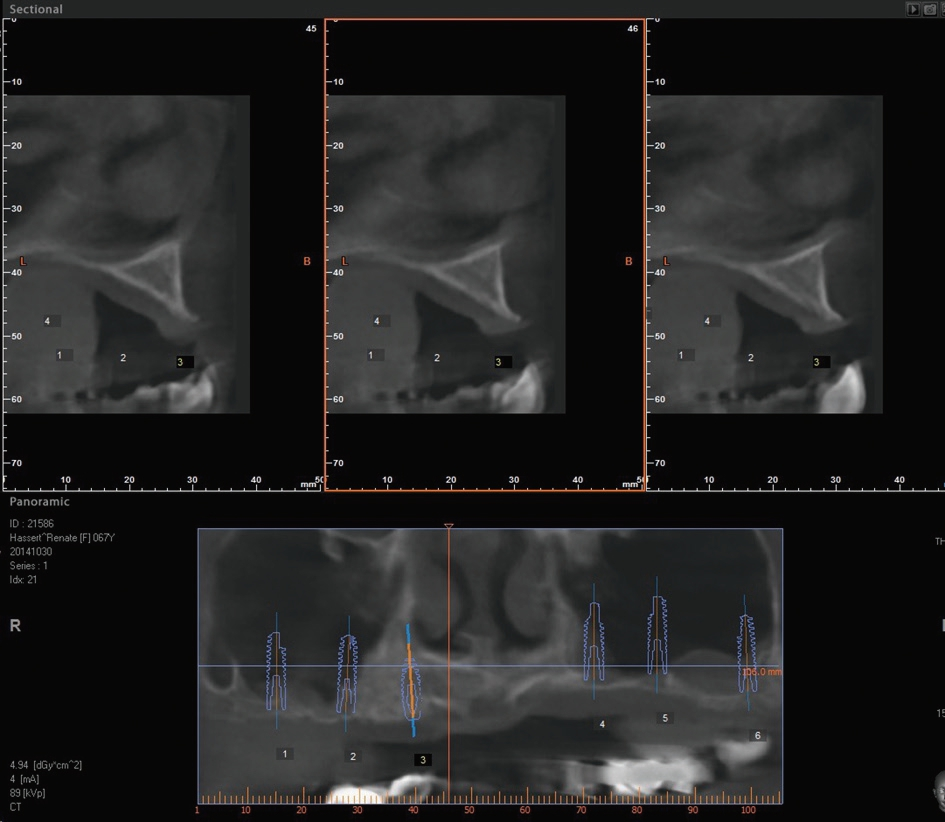

Der vorliegende Fall beschreibt die orale Rehabilitation einer 65 Jahre alten Patientin im Oberkiefer (Abb. 1 und 2). Der atrophierte Oberkiefer weist eine sagittale Stufe zum Unterkiefer auf. Dies macht eine komplett festsitzende Versorgung von vorneherein schwer umsetzbar. Die Patientin wünschte sich dennoch einen ästhetisch ansprechenden Zahnersatz und eine langzeitstabile Lösung. Die konservierende Behandlung des Unterkiefers wurde im Rahmen der ganzheitlichen Sanierung von uns ebenfalls geplant und durchgeführt.

Vor dem zweiten OP-Eingriff nach 4 Monaten wurde im Labor eine Bohrschablone angefertigt. Zudem wurde ein DVT angefertigt, um im Sinne eines Backward planning die ideale Implantatposition planen zu können. Bei Eröffnung des augmentierten Kieferbereiches zeigte sich im augmentierten Bereich eine gute Regeneration und Revaskularisierung des Knochens (Abb. 14 bis 17). Sechs Implantate konnten somit in den augmentierten Bereich (Astratech EV®, DENTSPLY Sirona, Mannheim) mit ausreichender Länge und Durchmesser in Form einer gleichmäßigen Pfeilerverteilung in den Kieferknochen Inseriert werden (Abb. 18).